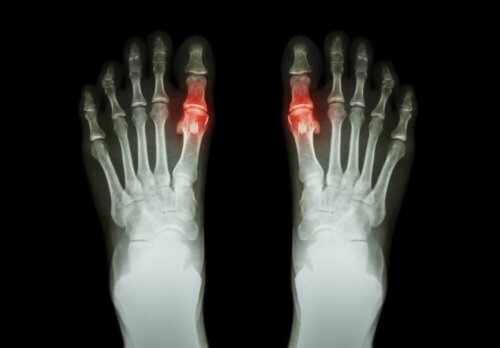

Artrit genellikle etkilenen eklem ya da eklemlerde ağrı ve hareket güçlüğü formunda ortaya çıkma eğilimindedir. Bazı durumlarda aynı bölgede sertlik ve şişmeyi de içerebilir. Sadece bir eklemi ya da aynı anda pek çok eklemi etkileyebilir. Ayrıca simetrik ya da asimetrik olabilir.

Her tür kendi partiküllerine sahiptir ve semptomların devam ettiği süre değişkenlik gösterir. Örneğin, romatoid artrit parmaklardaki eklemler gibi küçük eklemleri etkileyen simetrik bir artrit tipidir. Diğer yandan gut sadece bir eklemi etkileme eğiliminde olan bir artrit türüdür.